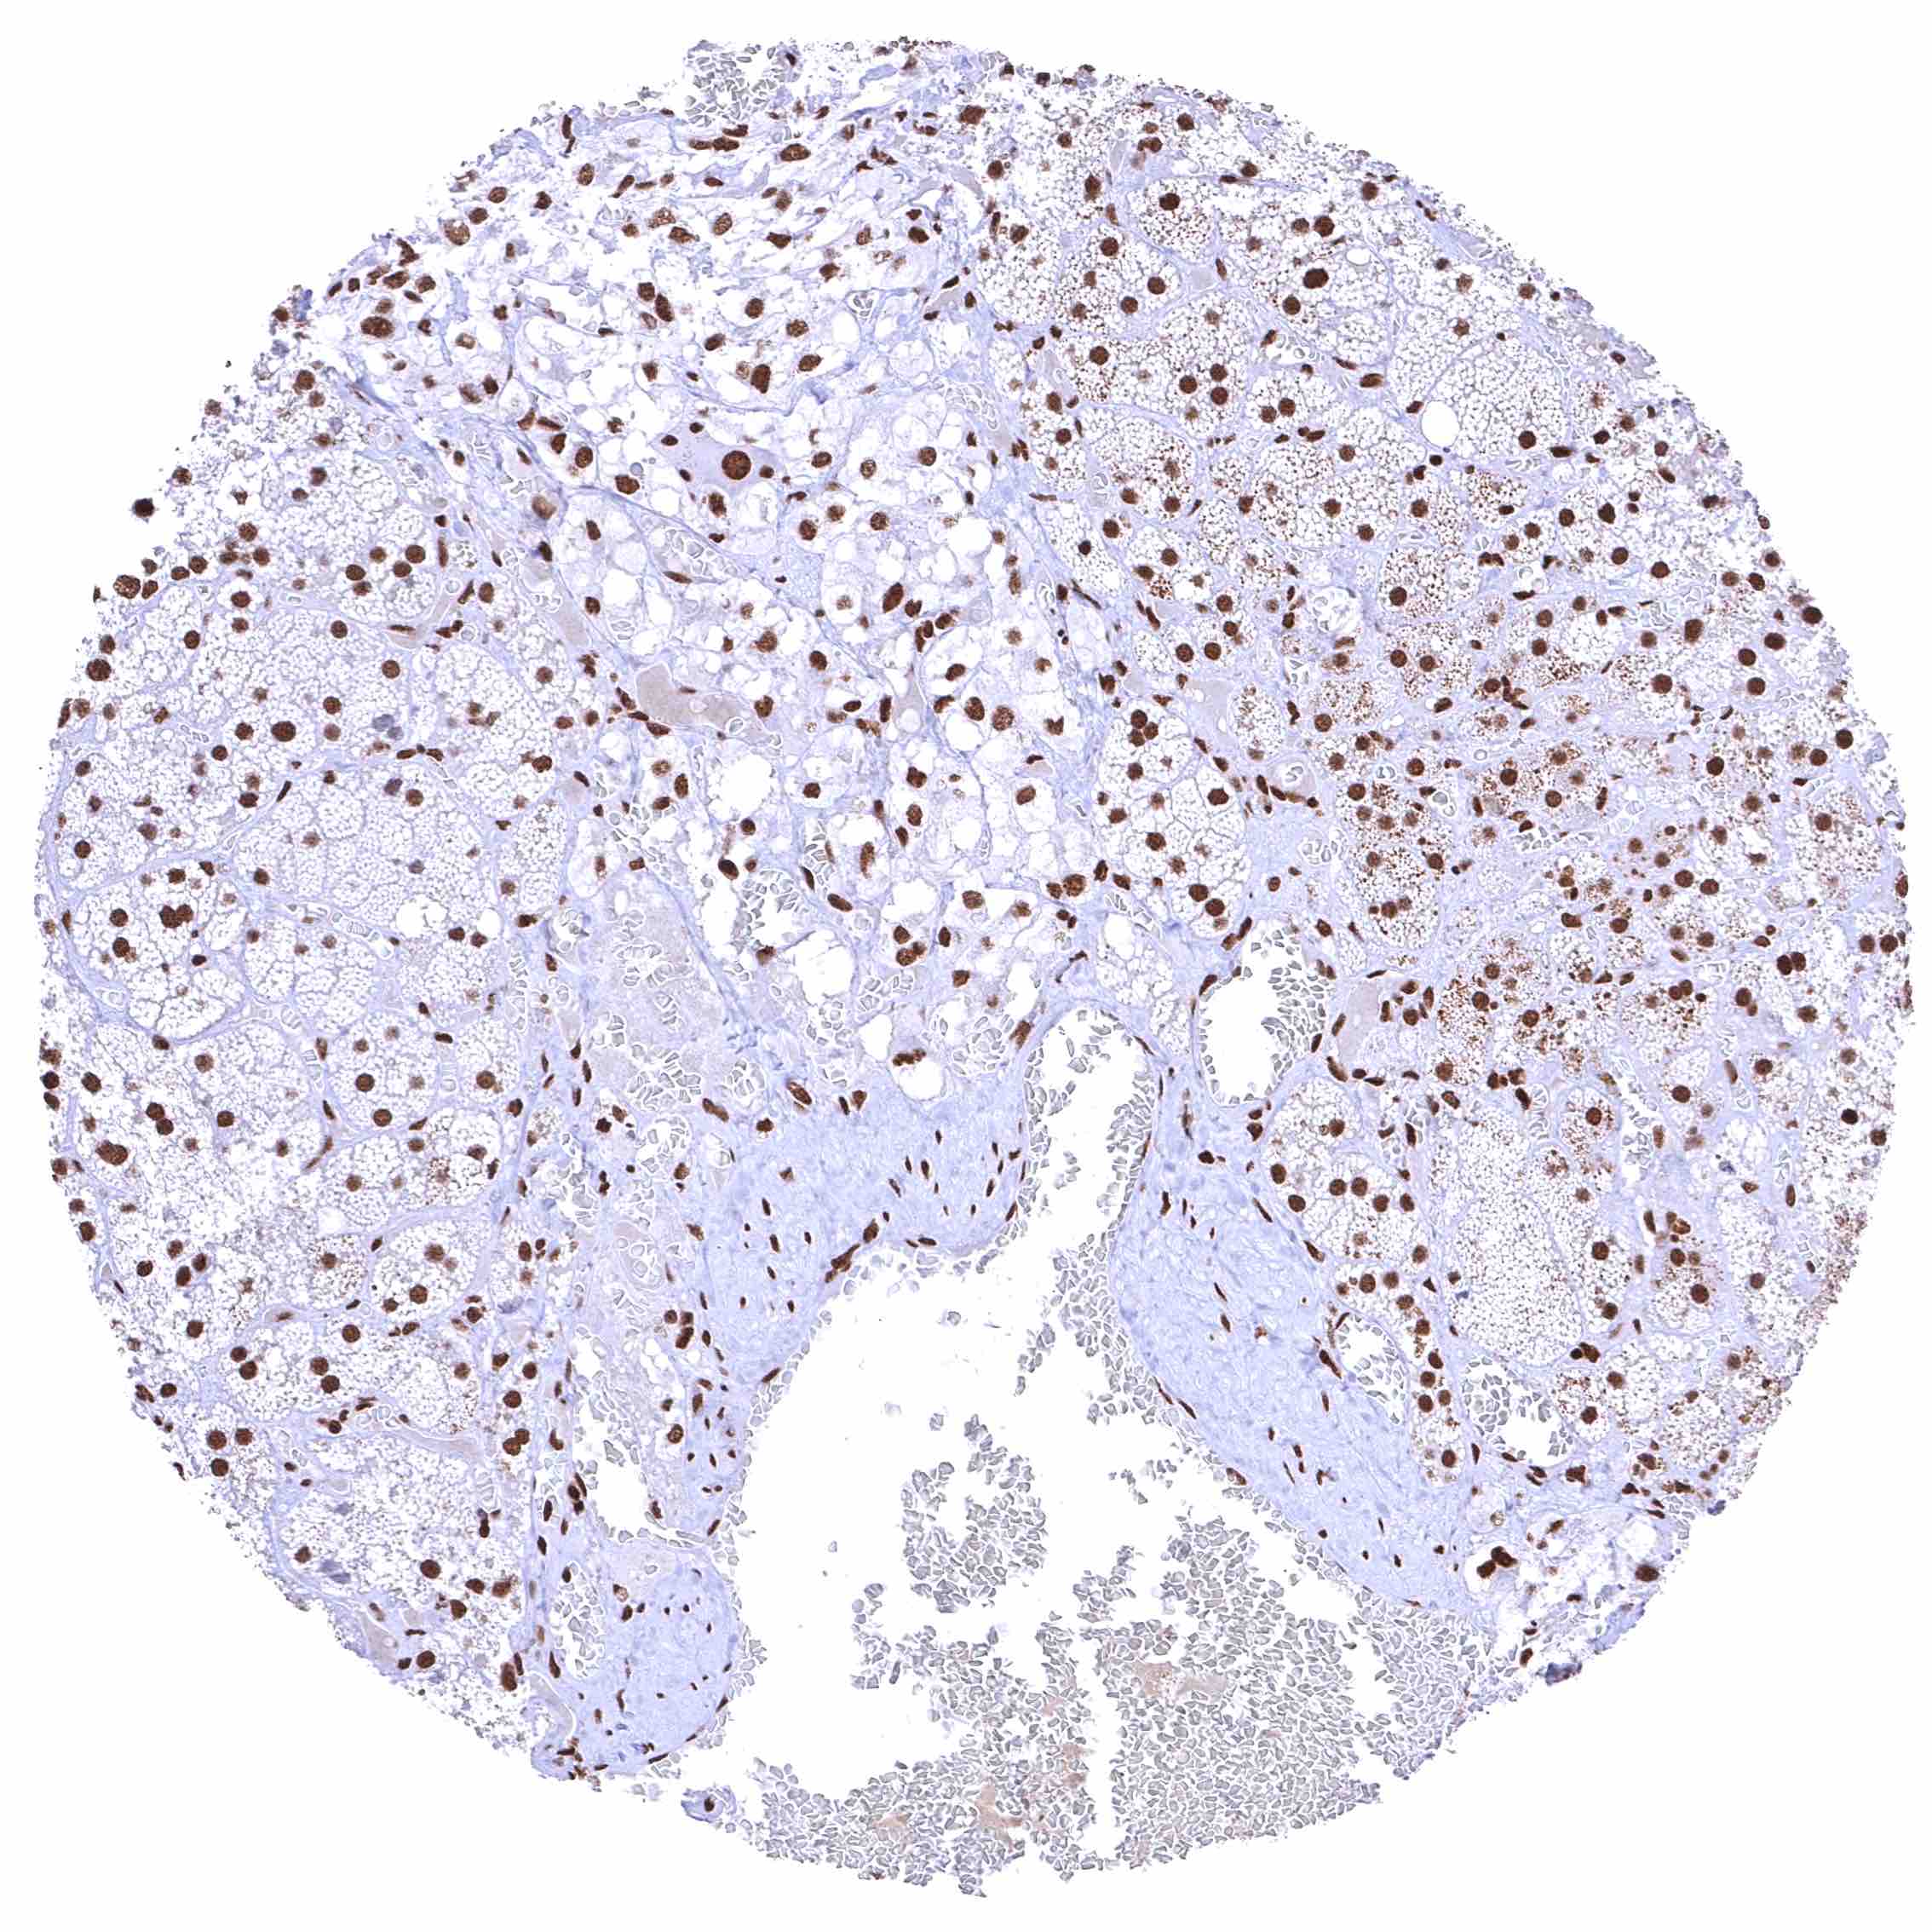

Testis – The level of nuclear BRD4 staining decreases with maturation of germ cells.